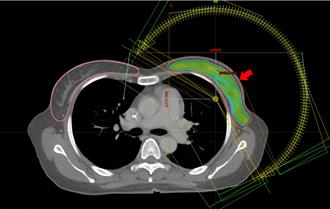

保住胸口爱的印记 医歼灭乳癌展开美丽图腾的守护战

1名40岁女性罹患左乳乳癌,但她不希望治疗破坏她胸部美丽的刺青,那是她爱的图腾。医疗团队在手术和放射治疗中,细心地保护她的刺青,澄清医院中港院区放射肿瘤科主任许维中表示,在25次光子刀放射治疗中,精确调控放射剂量,不仅成功保护刺青,后续检查也显示无癌细胞踪迹。这段疗程不仅挽救了她的健康,也保留了她对生命的信仰与爱。